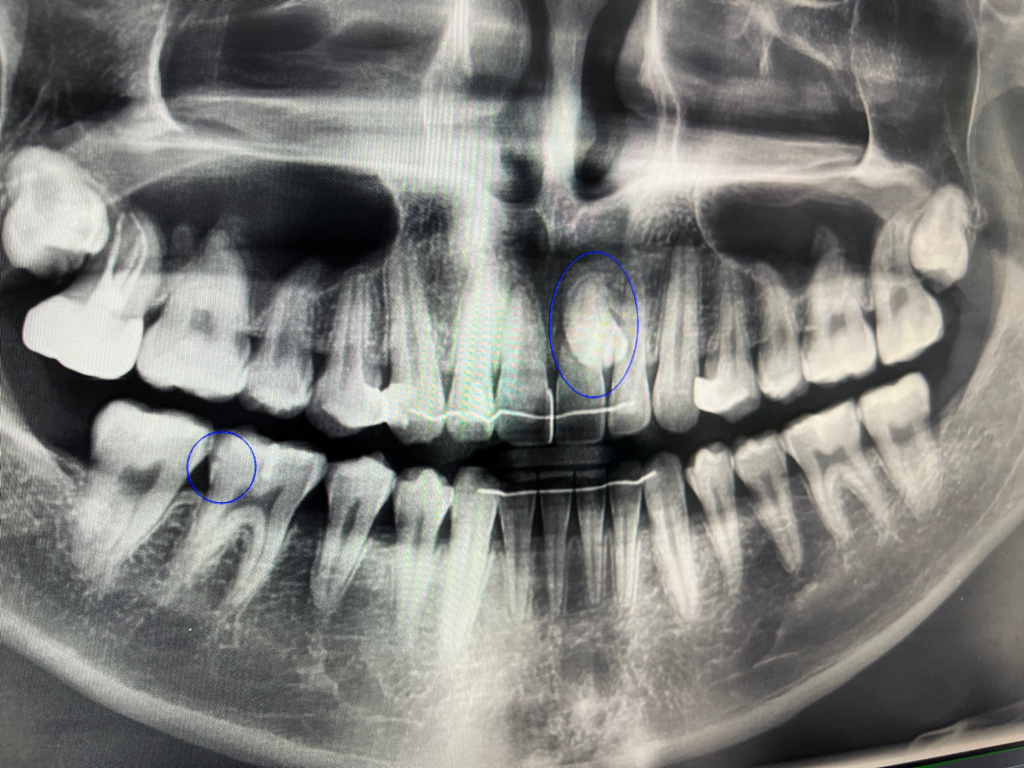

과잉치가 있는데 뽑아야 할까요?

윗니 중 앞니 쪽 뿌리 쪽에 과잉치가 있습니다.

그런데 오늘 간 치과에서는 저 치아가 치아 뿌리를 흡수하거나 물혹이 될 수 있다고 하더군요.

꼭 뽑아야 하는 종류의 치아인가요?

그리고 만약 뽑게 된다면 아무 치과에서나 뽑아도 될까요?

치아 뿌리를 흡수 시킬 수 있고 물혹이 될 수 있으나 발치가 쉽지 않으면 경과를 지켜보는 치아이기도 합니다. 즉 과잉치가 있다라는 것을 알고 주기적으로 치과 방문 후 해당 부위에 대한 추적관찰을 하더라도 괜찮습니다. 물론 선제적으로 뽑아주셔도 됩니다.

들으신대로 뿌리 흡수 혹은 감염원의 가능성이 있으므로 웬만하면 발치를 하시는 게 좋습니다.